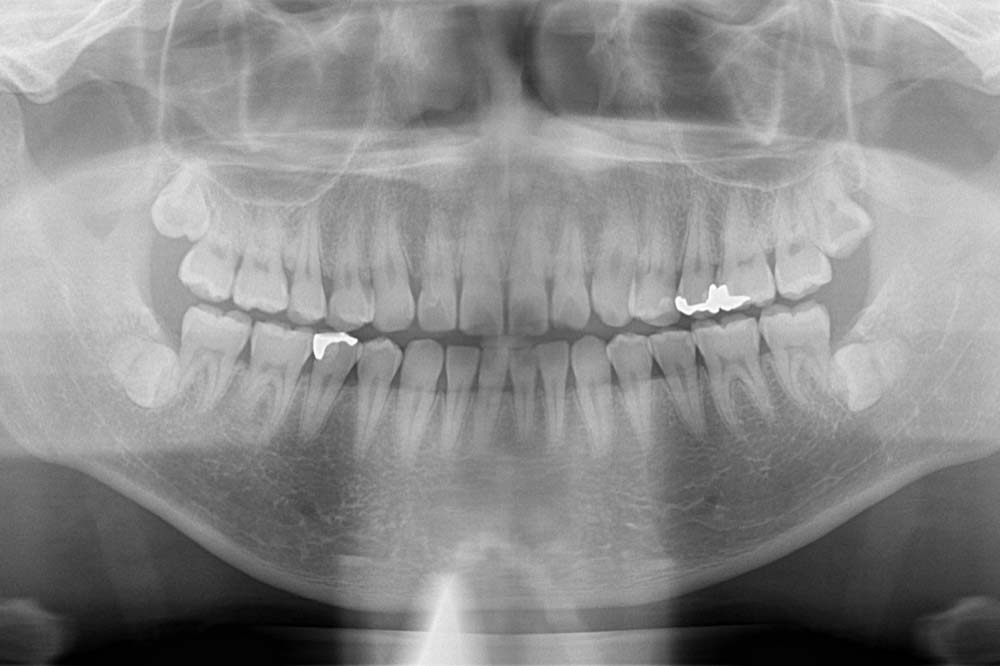

まずはレントゲンを撮影し、ご自身の親知らずの状態を確認することが大切です。

まずはレントゲンを撮影しご自身の親知らずの状態を確認することが大切です。

まずはレントゲン撮影や歯周病検査を行い、ご自身の状態を確認することが大切です。